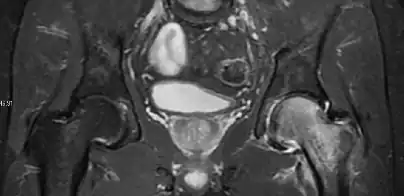

Intra-articular osseous causes of pain include several conditions: avascular necrosis (AVN), transient osteoporosis of the hip (TOH), tumors, and stress or insufficiency fractures. All these entities may present with a pattern of bone marrow edema characterized by decreased signal intensity on T1 weighted images and increased signal intensity on fluid sensitive sequences, such as fat saturated T2-weighted or STIR images. When there is no evidence of a focal lesion associated with the edema pattern, TOH is suspected. When a band of low intensity is seen inside the edematous area, the shape and length of this band become important. It is generally convex to the articular surface in the case of subchondral stress or insufficiency fractures, whereas it is concave, circumscribing all of the necrotic segment, in cases of AVN. When doubts do persist, gadolinium-enhanced MRI tends to show that the proximal portion beyond the band is enhanced in fractures but is not in AVN.[1]

MRI has been shown to have 100% sensitivity and specificity in prospective studies of occult hip fractures. These fractures were diagnosed by bone marrow edema and a low signal fracture line, mainly on T1 or T2 weighted images (Figure 10).[1]

Figure 10: